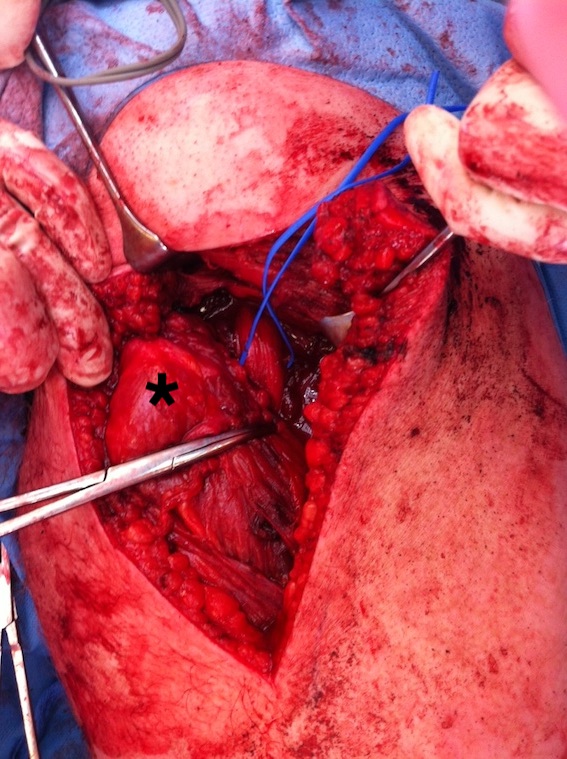

Hamstring (*) with sciatic nerve lateral to hamstring (blue vessiloop)

Identify and release proximal hamstring tendon

Stump of the conjoint tendon (*)